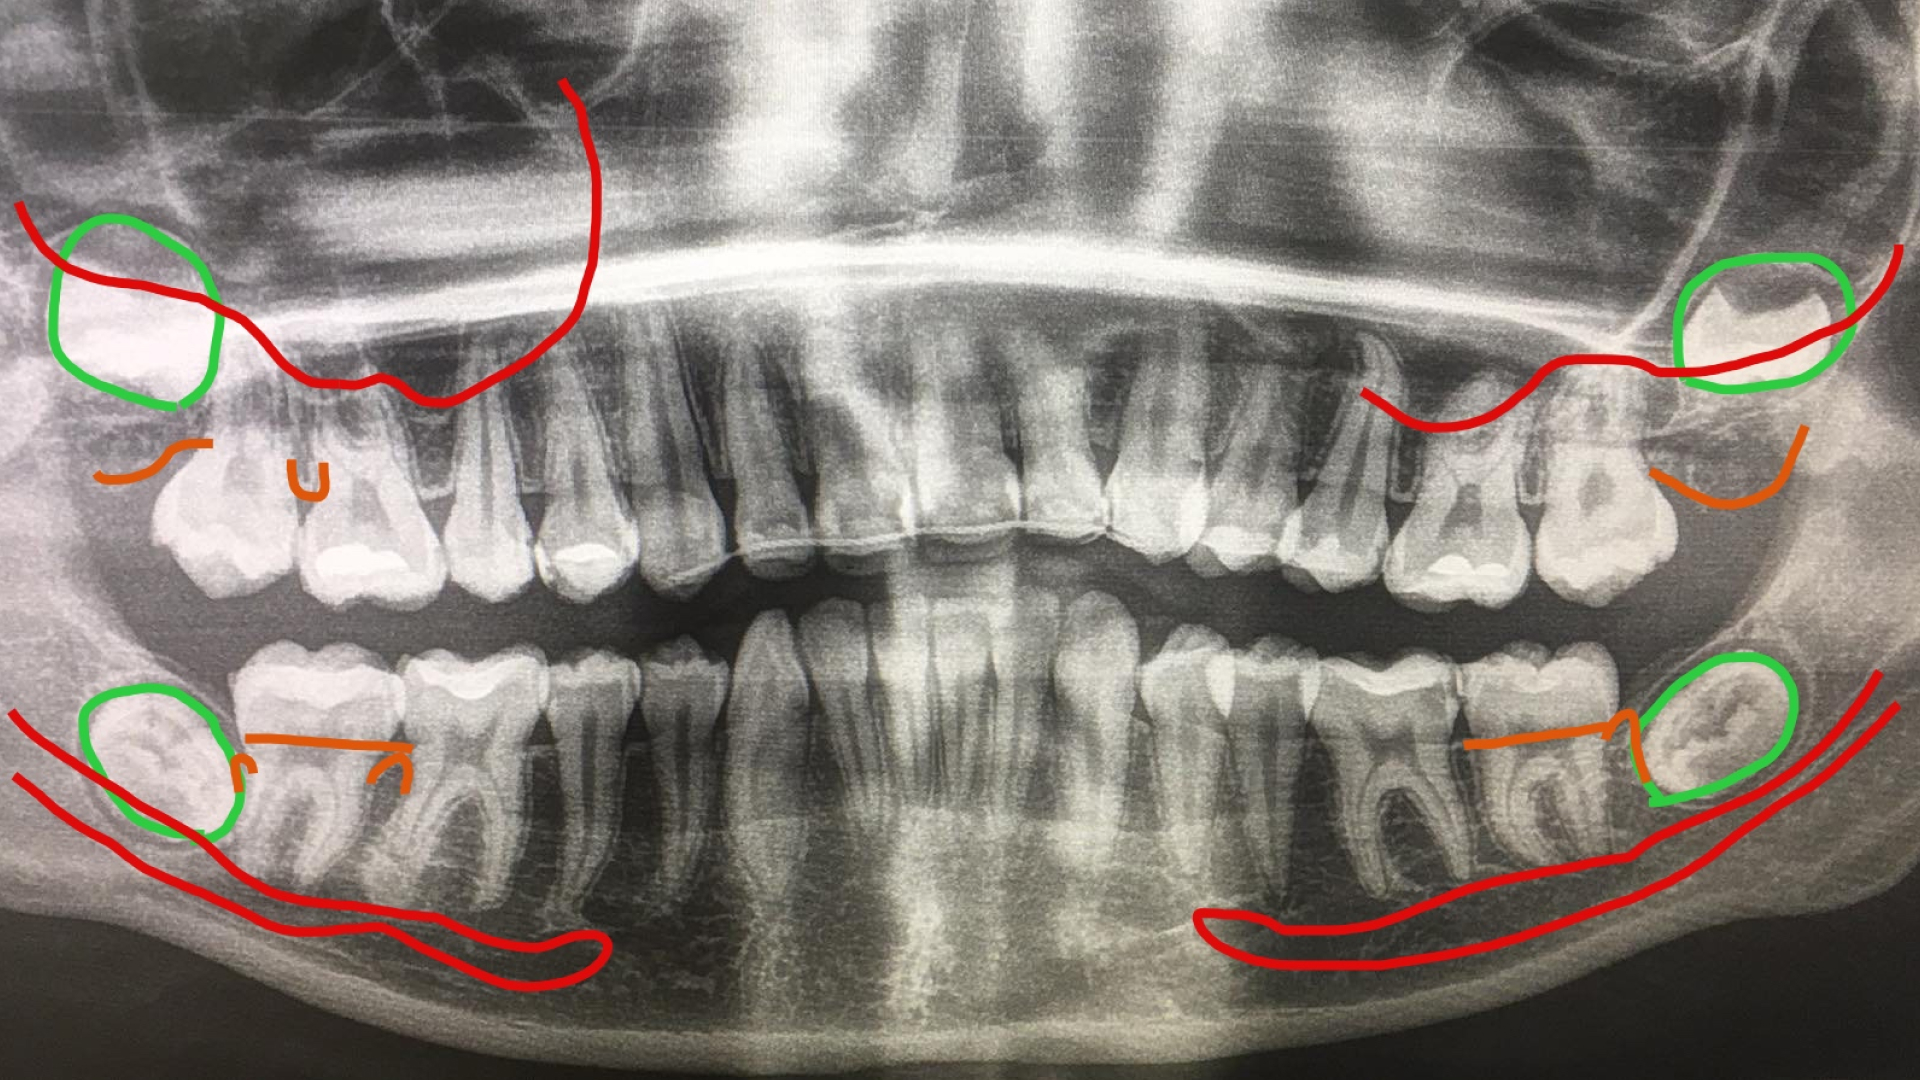

«Видалення третіх молярів 481» І. Прощин